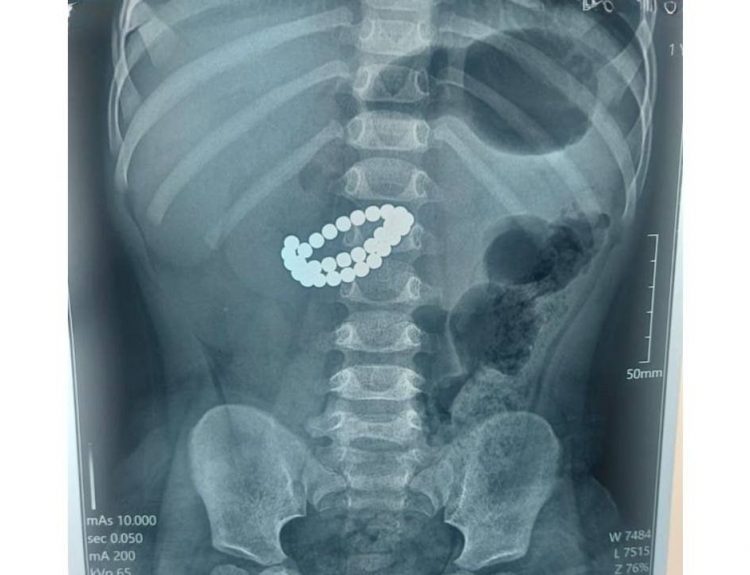

«Ішектері тесіліп кеткен»: Алматыда дәрігерлер 31 магнит жұтқан сәбиді аман алып қалды

Алматыда дәрігерлер 1 жас 9 айлық сәбидің ішегінен 31 магнитті алып шықты. Бүлдіршіннің ішектері тесіліп, перитонит асқынған.